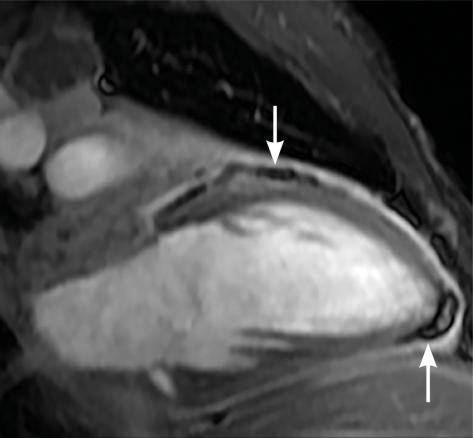

L’imagerie montrait : sur la tomodensitométrie (TDM) thoracique une miliaire tuberculeuse pulmonaire et des adénopathies médiastinales ; sur l’imagerie par résonance magnétique (IRM) du rachis une spondylodiscite T11-T12 (fig. 1 ) ; sur la TDM abdominale des abcès paravertébraux de T9 à T12 le long des psoas (fig. 2 , flèches blanches) et des lésions micronodulaires hépatiques multiples (fig. 2 , flèche jaune) ; sur l’IRM myocardique des signes de péricardite (fig. 3 , flèches). La ponction lombaire montrait une méningite. Un tuberculome était visible sur l’IRM cérébrale, entouré d’un œdème périlésionnel (fig. 4 ). Le diagnostic de tuberculose disséminée était prouvé par polymerase chain reaction sur une ponction d’abcès. Compte tenu de l’atteinte neuroméningée, un traitement adjuvant par corticothérapie s’imposait dans le cas présent, de même qu’une antibiothérapie de 9 à 12 mois.1